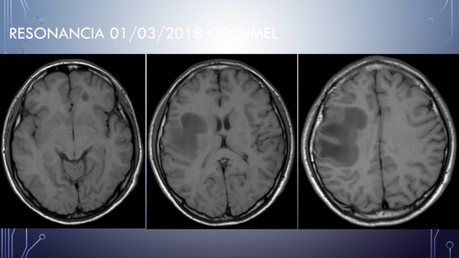

Deterioro neurológico: parálisis de miembro superior izquierdo y hemiparesia izquierda.

Ingresa al HGZ en Cancún, Q. Roo, con traslado a la UMAE Mérida